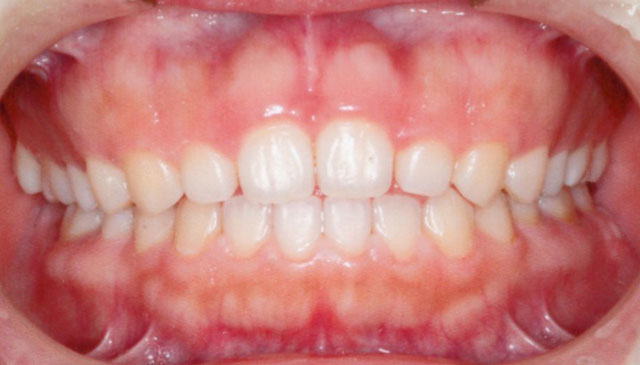

治療期間は1年11か月で、その後は保定へ移行。

治療後の患者さんの感想

発音漏れがなくなった。 話が聞きやすくなったと言われ、うれしい

- 治療期間及び回数

- 1年1か月/13回(月1回程度の通院)